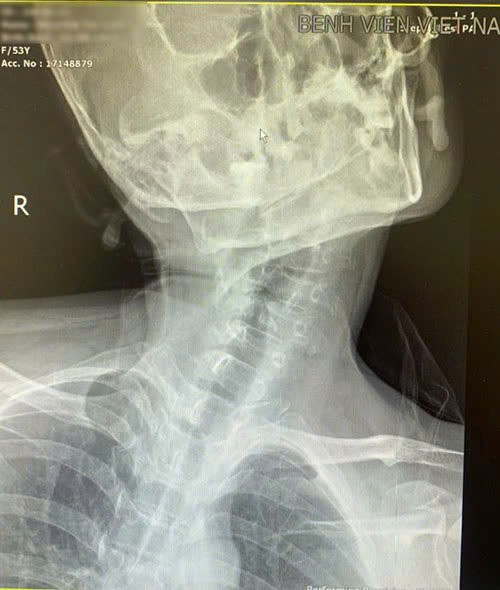

Tình trạng vẹo cột sống cổ của người bệnh - Ảnh BVCC

Đây là ca lâm sàng phức tạp do biến dạng giải phẫu vùng cổ gây hạn chế nghiêm trọng khả năng ngửa đầu và quan sát thanh môn, làm tăng nguy cơ thất bại khi đặt nội khí quản bằng phương pháp thông thường.